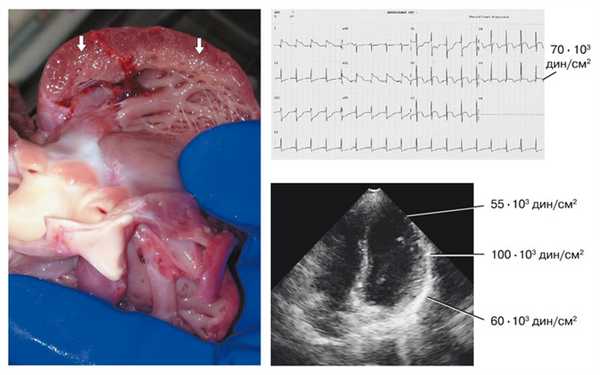

Определение внутримиокардиального напряжения [7] проводили по морфометрическим показателям левого желудочка по результатам ЭхоКГ при сканировании по длинной оси желудочка в М-режиме (рис. 1).

Рис. 1. Принцип определения морфометрических показателей левого желудочка (ЛЖ) для определения его внутримиокардиального напряжения.

1 - IVSd (межжелудочковая перегородка в диастолу), 2 - Dd (диаметр ЛЖ в диастолу), 3 - LVPWd (толщина задней стенки ЛЖ в диастолу), 4 - Ds (диаметр ЛЖ в систолу), 5 - LVPWs (толщина задней стенки ЛЖ в систолу). Ао - аорта, LA - левое предсердие.Для вычисления внутримиокардиального напряжения (σs) применялась формула:

σs = (P · Dd/2)/[2LVPWd · (1+LVPWd/Dd)] дин/см² · 10³,

где Р дин/см² - максимальное давление в левом желудочке мм рт.ст. · 1,333 · 10³; Dd - диаметр левого желудочка в диастолу (см); LVPWd - толщина задней стенки левого желудочка в диастолу (см). Максимальное давление (Р) в мм рт.ст. в полости левого желудочка определяли по формуле G. Johnson и соавт. [9]: P мм рт.ст. = 225 · LVPWs : Ds.Формула выведена авторами при сопоставлении результатов зондирования сердца у пациентов в возрасте от 2 до 20 лет (средний возраст 7 лет). Коэффициент корреляции между ожидаемой величиной, рассчитанной на основании ЭхоКГ, и результатами зондирования при различных патологических состояниях колеблется от 0,87 до 0,89. Для перевода мм рт.ст. в дин/см² полученную величину умножали на 1,333 · 10³.

Величина σs оказалась весьма близкой в различных возрастных группах, что особенно заметно при построении линии тренда (таблица 1, рис. 2).

Таблица 1. Параметры распределения детей разных возрастных групп по величине внутримиокардиального напряжения (σs).

Возраст Объем совокупности Среднее по совокупности

значение σs дин/см² · 10³Стандартное отклонение 1 мес 11 185 13 3 года 14 143 21 6 лет 6 200 17 12 лет 13 159 21 14 лет 14 165 24 ![Диаграмма величины внутримиокардиального напряжения у детей в разных возрастных группах]()

При сопоставлении групп средняя величина внутримиокардиального напряжения составила около 170 · 10³ дин/см².

Мы сопоставили полученные значения σs у здоровых детей с показателями, рассчитанными у детей с ишемией миокарда. У детей с ишемией миокарда σs составляла 45-70 · 10³ дин/см², не превышая 100 (рис. 3).

Рис. 3. Эхографические, электрокардиографические и морфологические проявления ишемии миокарда. На макропрепарате в левой части рисунка хорошо виден ишемизированный слой миокарда (стрелки). Справа вверху - ЭКГ ребенка с ишемией миокарда и показателем σs 70 · 10³ дин/см². В нижней правой части рисунка - эхограмма левого желудочка с зонами гипокинезии. В верхушечном отделе σs = 55 · 103 дин/см², в средней трети желудочка, более благополучной, - 100 · 10³ дин/см², в базальном отделе - 60 · 10³ дин/см².

Как видно из представленных таблицы и рисунков, показатели σs оказываются существенно снижены при ишемии миокарда.